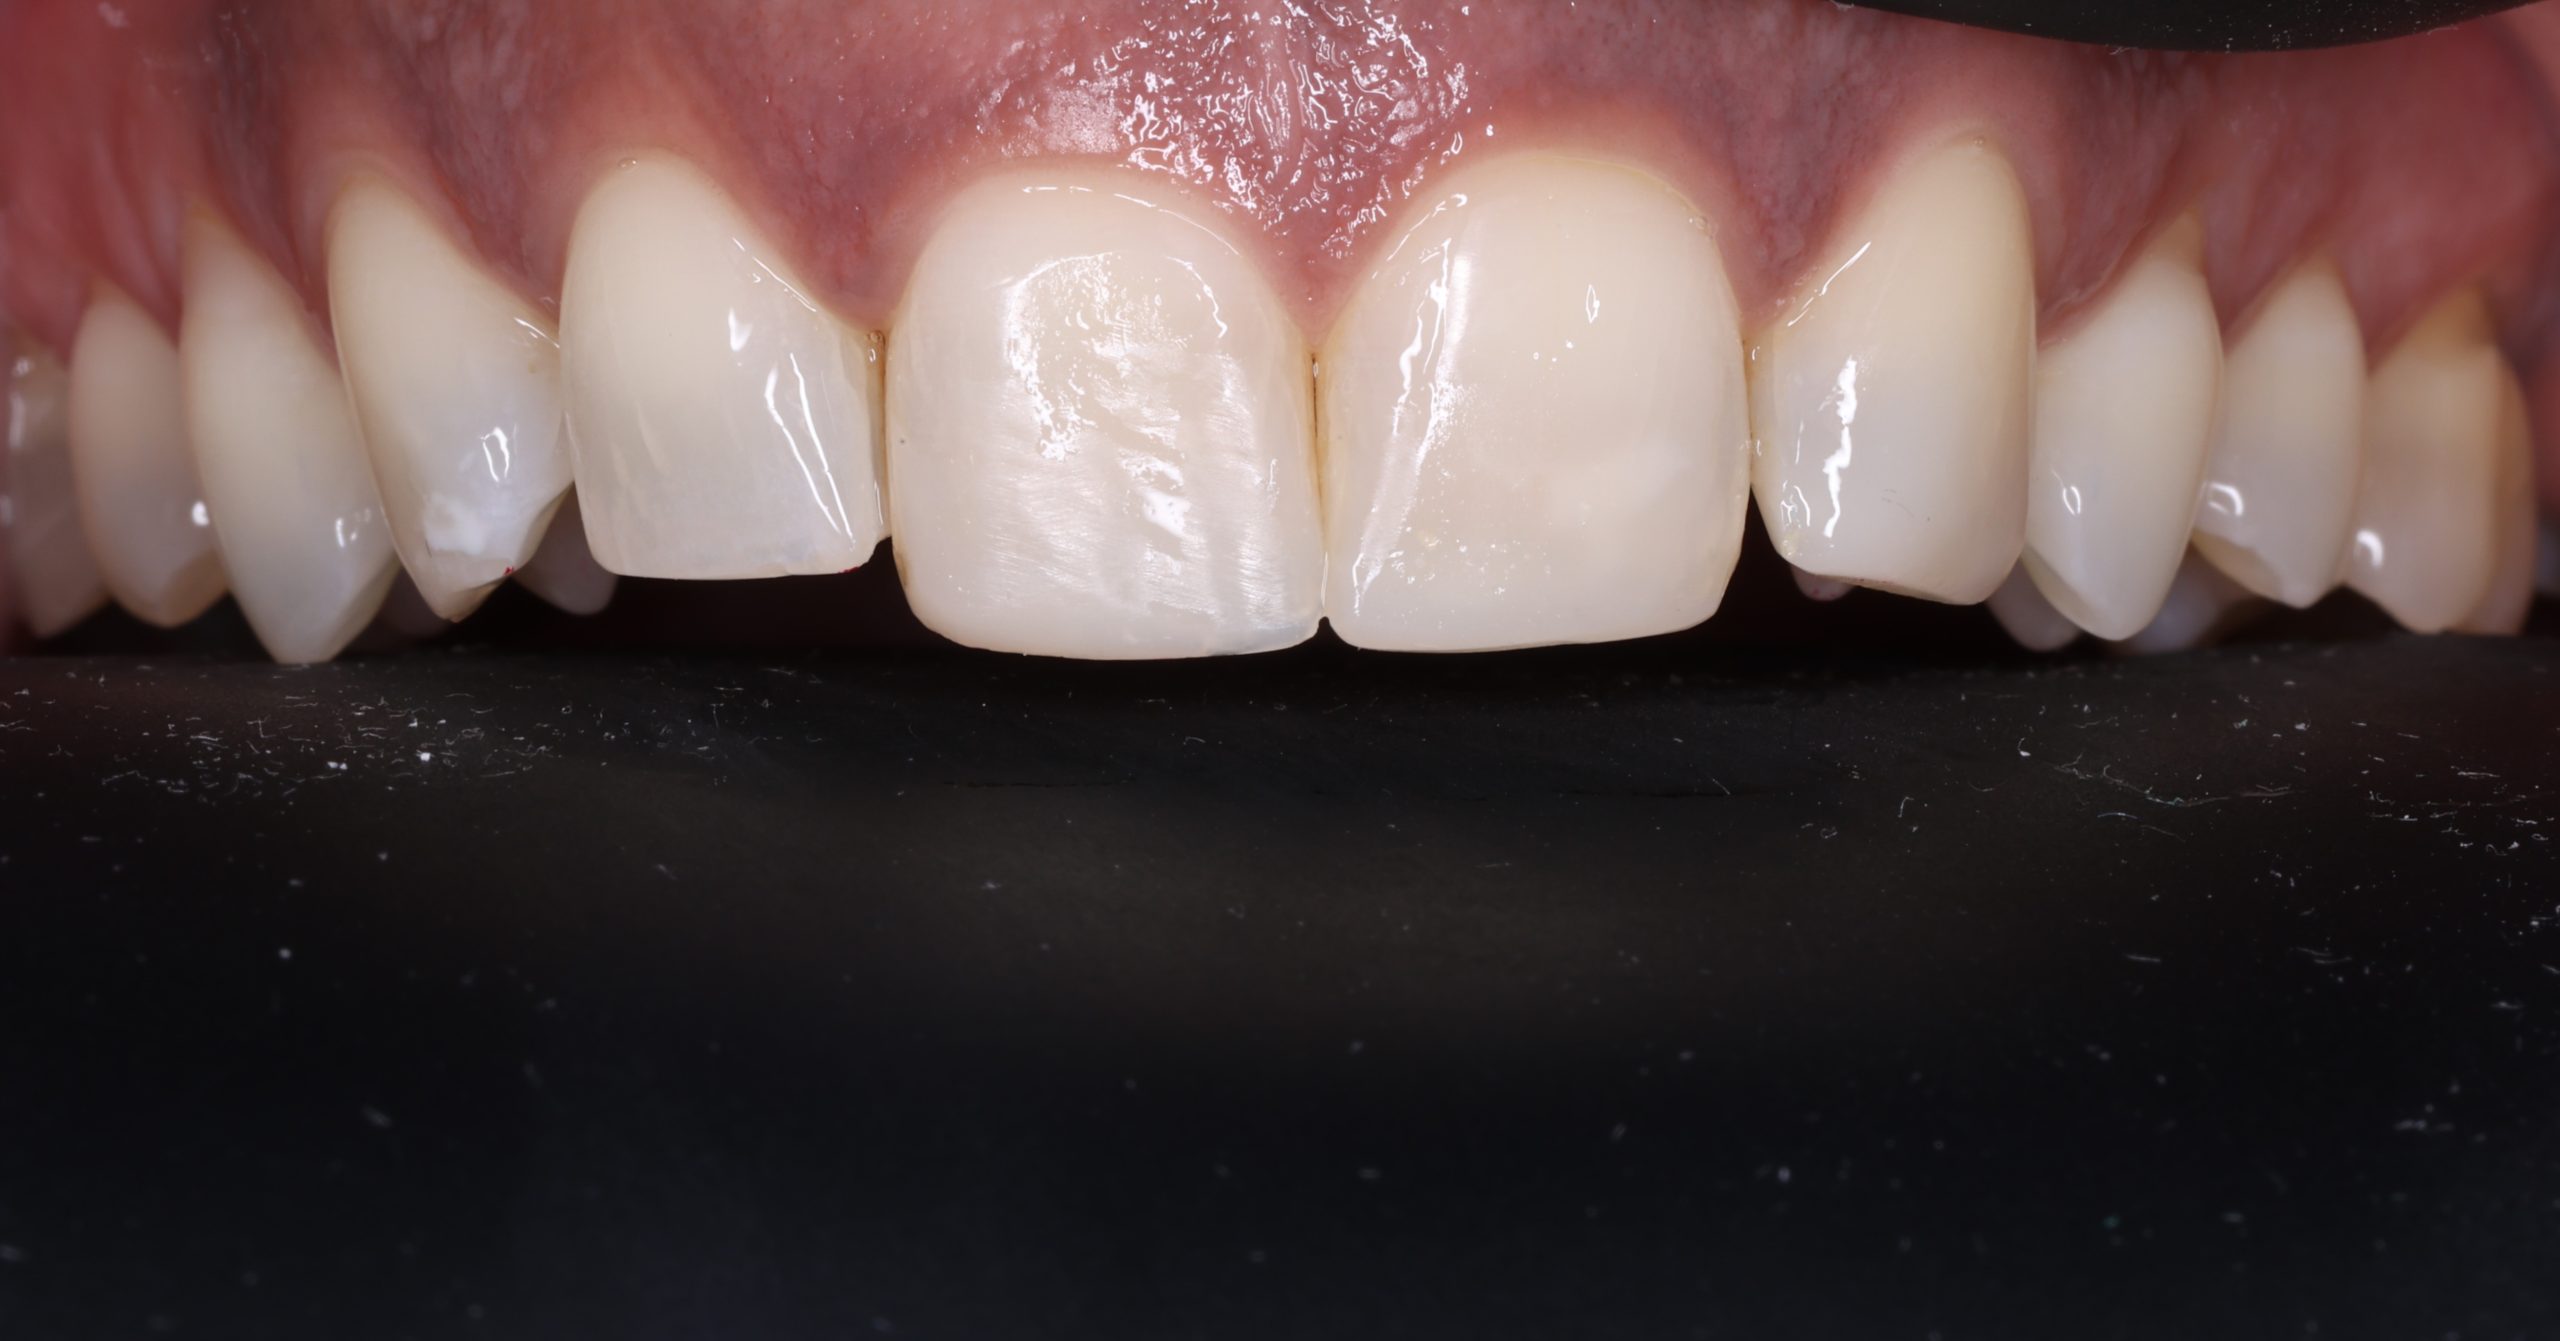

• fixing chipped or worn edges

The tooth-coloured resin is applied in thin layers and shaped carefully to match natural anatomy. For front-tooth work, we may combine several shades for a lifelike result.

The material matches your enamel, blending into the smile with virtually invisible transitions.

Bonding preserves healthy enamel because it adheres to the tooth instead of requiring extensive reshaping.